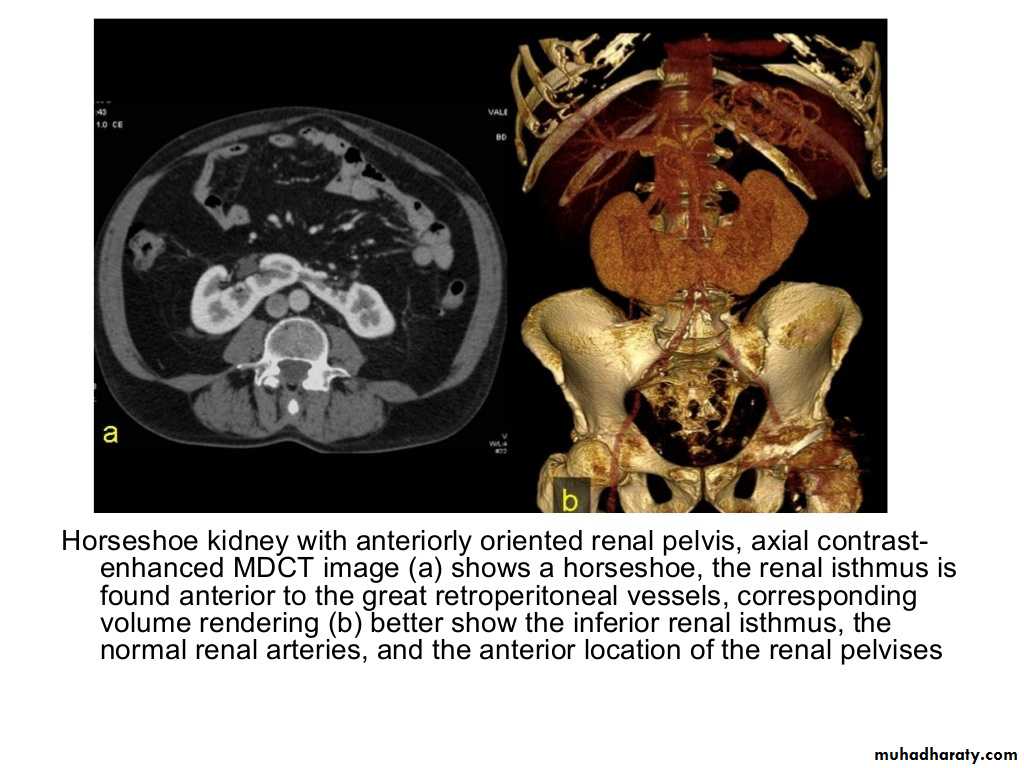

IVU shows

1. The kidneys at low position .2.Close to the spine with long axis parallel to the spine

3. Malrotation manifested by medially directed calyces.

4- The renal pelvis and ureters are anterior and lateral in position.

5- Hydronephrosis and calculi highly associated.